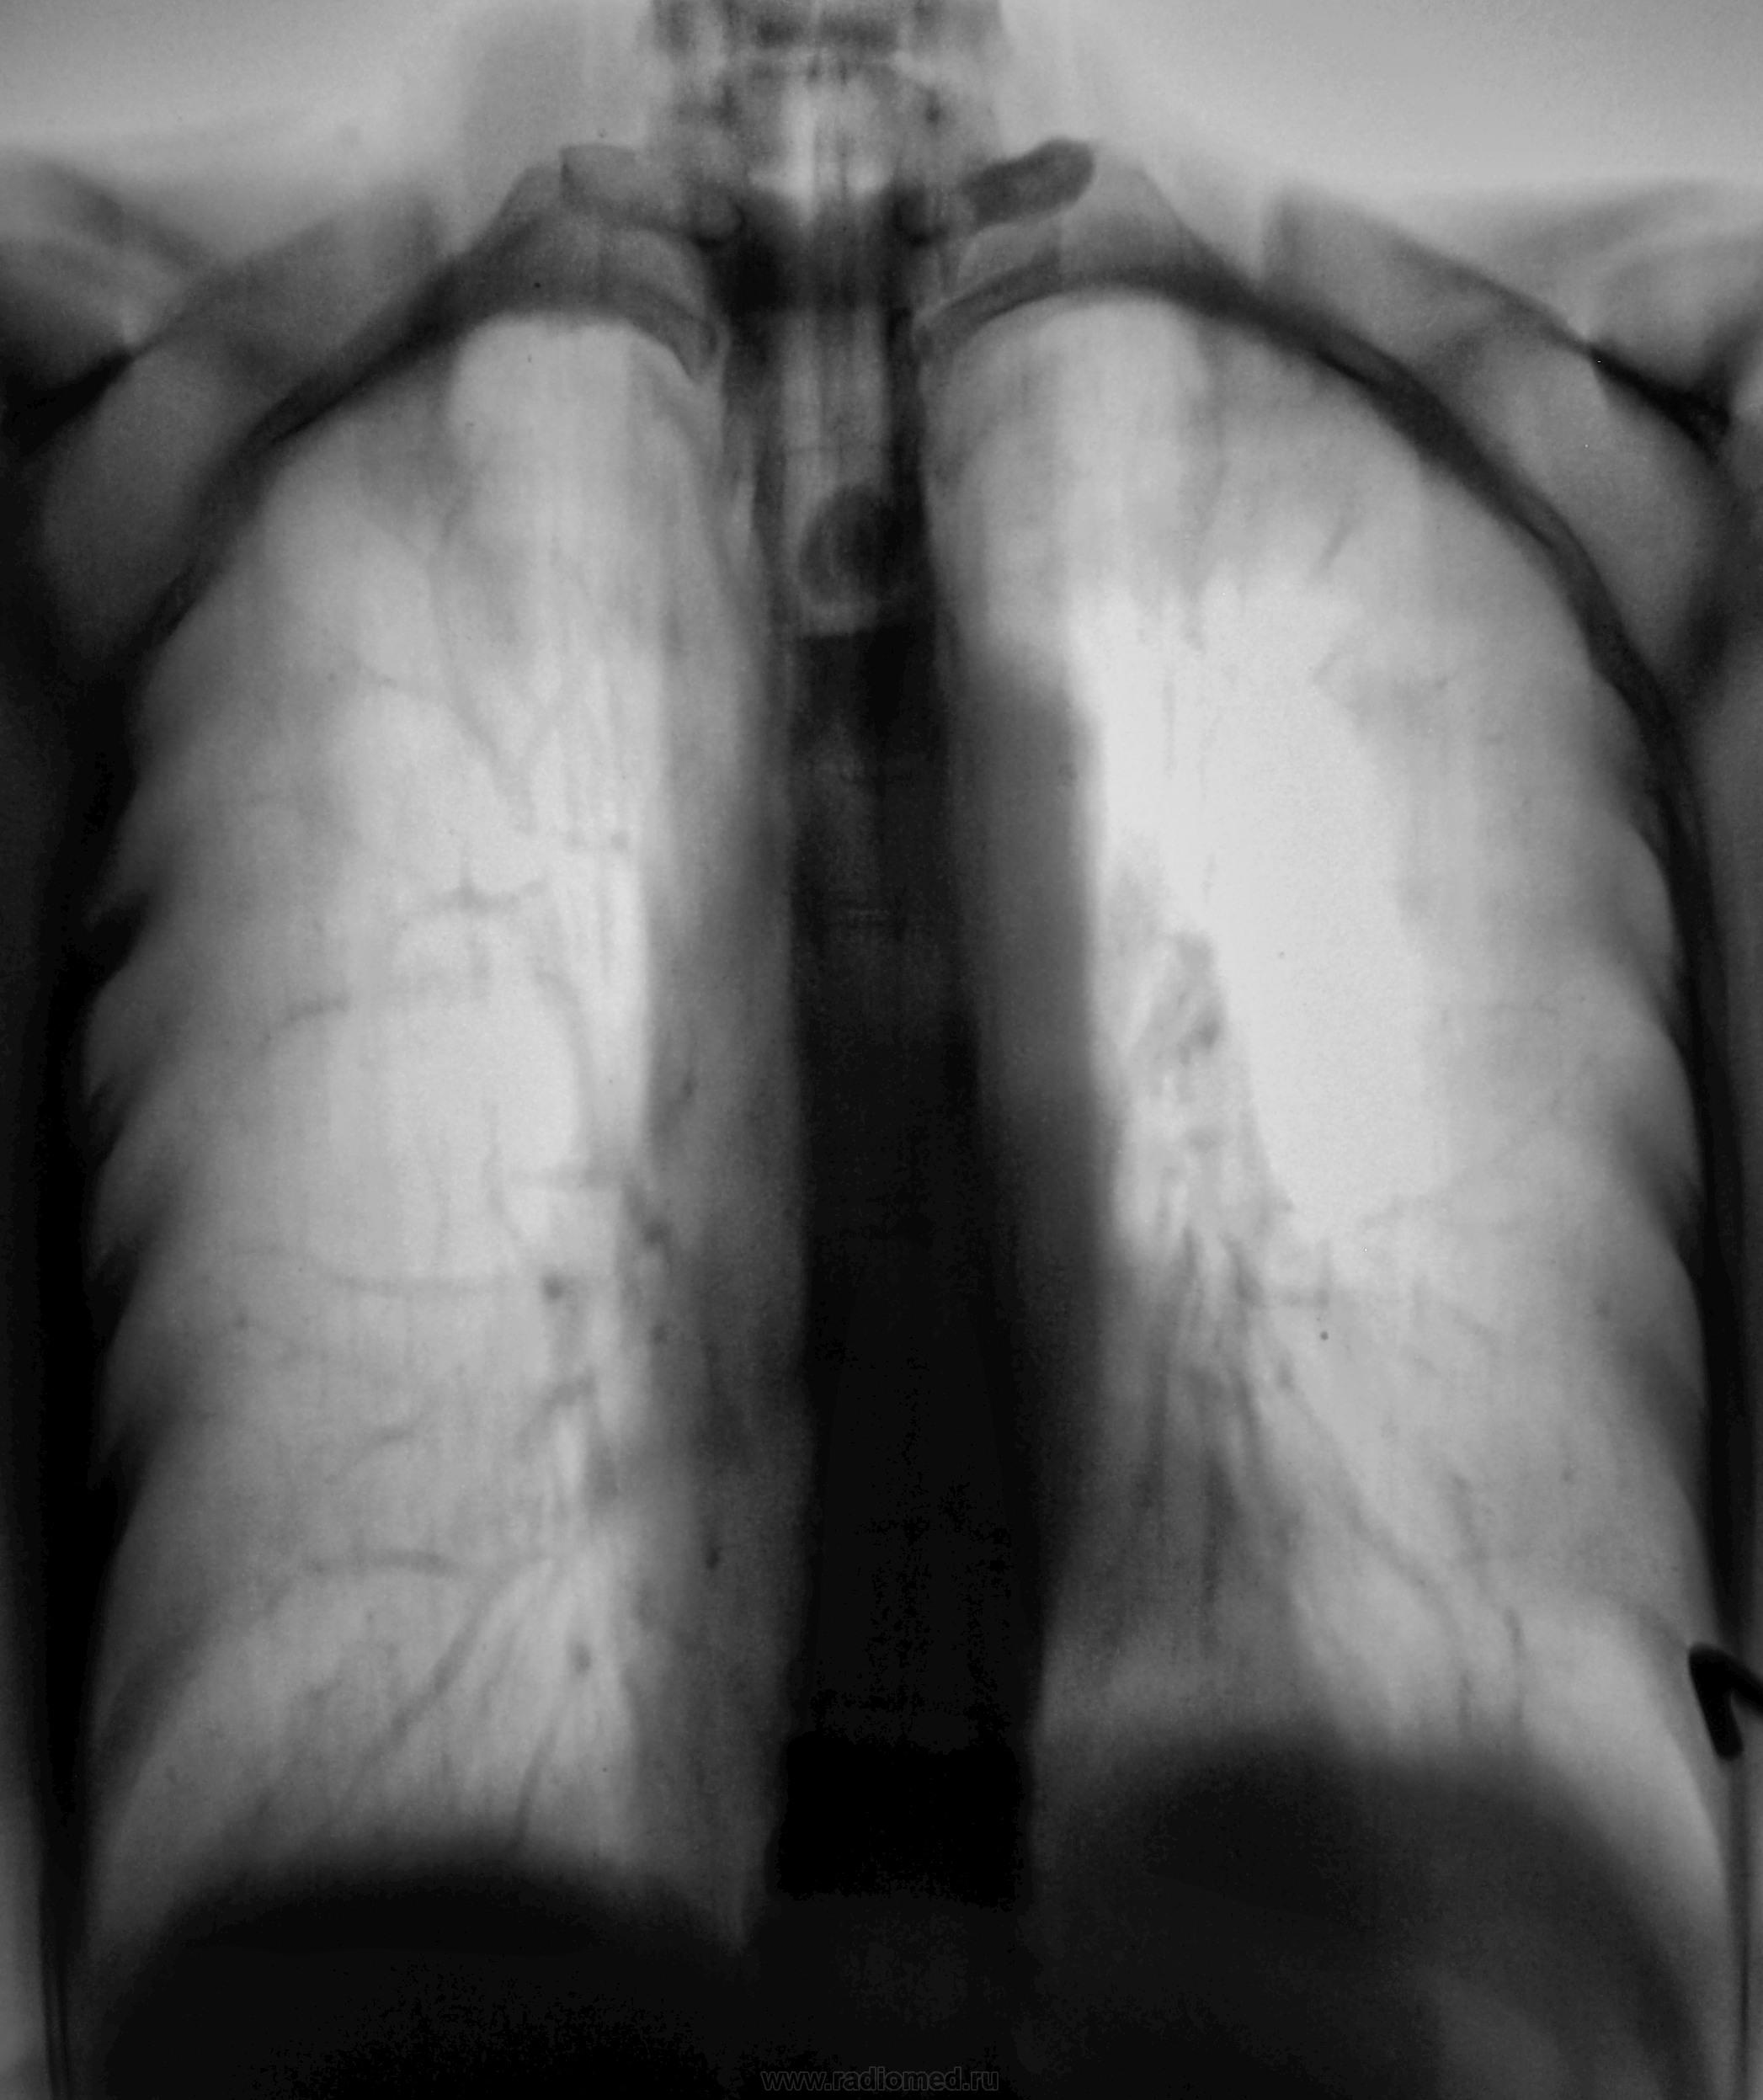

Глядя на позвонки, что-то всплыл термин "педжетоидный позвонок". Не помню, из какой оперы?

Пациентка 3 года тому была прооперирована по поводу рака молочной железы....

а клиники на тему мтс в кости нет?  я не видел линейных томограмм трубчатых костей с мтс, но позвонки немного просятся на такой невеселый диагноз

Пока клиники, как таковой нет, мы зацепили её с флюшки.

Год тому пациентка с семьёй попала в ДТП, была, тогда и клиника компрессионного перелома в поясничном отделе позвоночника, лежала она в хирургическом отделении.  На настоящее время у ней, конечно, бывают боли в пояснице, но это расценивается, как состояние после компрессионного перелома...

По всей видимости, метастазы из молочной железы.

в рёбра, плеч. кость и в позвоночник? 2 версия - Педжет.

Хорошая версия, и имеет право на жизнь. Только рак молочной железы верифицирован (биопсия).